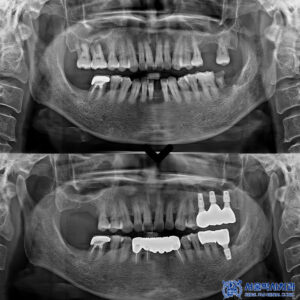

우선, 심한 치주염이 진행된 앞니 두 개를

발치한 뒤 바로 임플란트를

식립하는 방식으로

치료 계획을 세웠습니다.

다만, 환자분의 경우

치조골이 많이 부족한 상태여서

임플란트 식립과 동시에 뼈 이식도

함께 진행하기로 했습니다.

치료 후 2개월이 지나고 임플란트가 잇몸과

뼈에 잘 자리 잡았는지 확인한 뒤

최종 보철물을 세팅하는

단계로 넘어갔는데요.